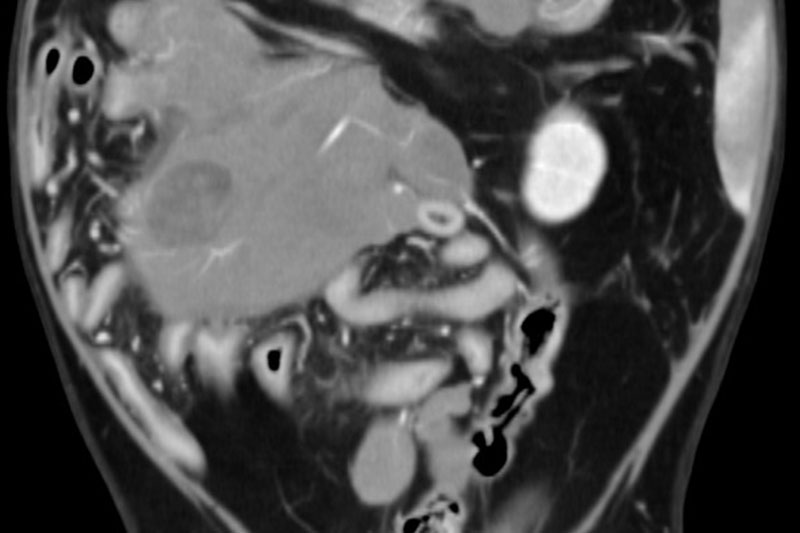

| 복부 | 간, 비장, 신장, 위장관 종양 및 결석, 부신, 림프절 등 |